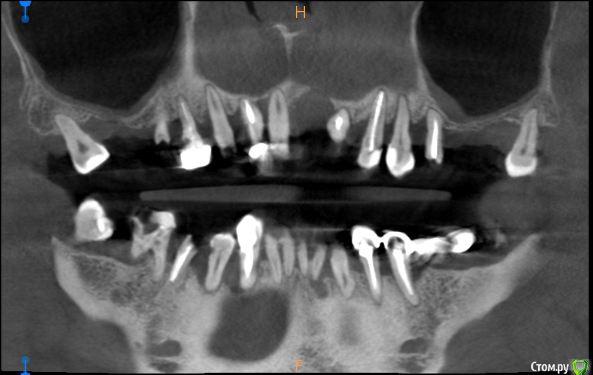

St. Опубликовано 17 апреля, 2018 Поделиться Опубликовано 17 апреля, 2018 Обзорные срезы ( верх, низ, топография нижнечелюстного нерва), дефект в обл 21 Ссылка на комментарий